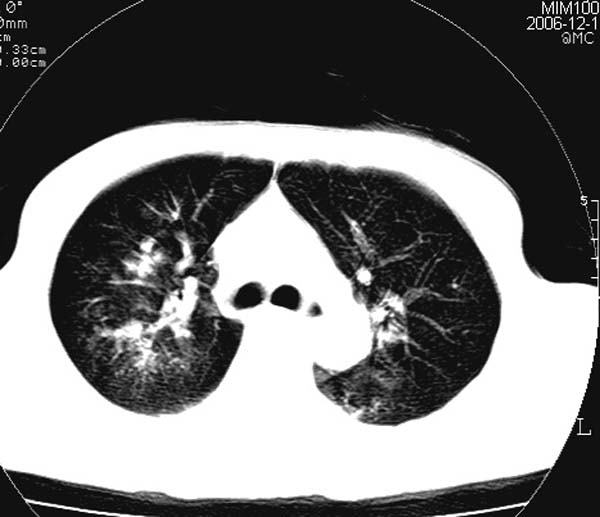

此病人是摔伤后12小时,38岁,无结核病史。谢谢

对不起各位,学着发图片,所以没有发全。此病人是摔伤后12小时,38岁,无结核病史。谢谢!

影像必须密切结合临床!此病例首先考虑肺撕裂伤,间质性改变为主,右侧有创伤性湿肺表现。鉴别诊断诸位大虾已经说得非常ok了。

结合病史,考虑肺挫伤可能,双侧少量胸腔积液.建议短期复查.

肺挫裂伤是肯定有。原来可能有结核或尘肺

影像必须密切结合临床!此病例首先考虑肺撕裂伤,间质性改变为主,右侧有创伤性湿肺表现。鉴别诊断诸位已经说了。

此病例首先考虑肺撕裂伤,间质性改变为主,右侧有创伤性湿肺表现,可短期治疗复查。